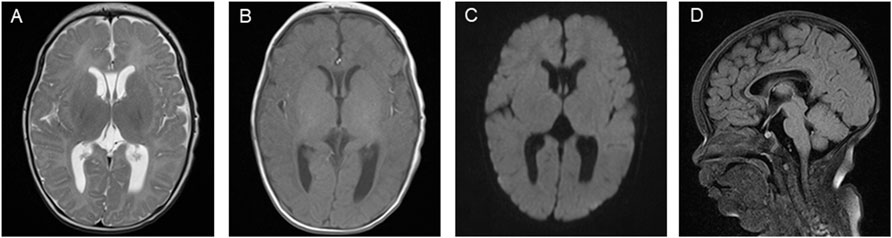

These results led the patient to be diagnosed with D-BPD type II caused by the novel compound heterozygous mutation c.1145G>A (p. Gly382Asp)/c.1193C>G (p.Ser398*) in exon 13 of the HSD17B4 gene. Before discharge, a repeated MRI was performed at 51 days of admission (Figure 3). This showed symmetrical bilateral cerebral hemispheres with normal gray and white matter signal intensities (Figure 3A). T1-weighted images (T1WI) revealed increased signal intensity in the posterior limb of the internal capsule, and the cavum septum pellucidum was present (Figure 3B). Diffusion-weighted imaging (DWI) showed no obvious abnormal signal (Figure 3C), and a fluid-attenuated inversion recovery (FLAIR) sequence showed that the corpus callosum genu and body were in normal morphology (Figure 3D). On the 52nd day of life, the patient was discharged with normal laboratory test results of blood routine, coagulation function, blood glucose, blood ammonia, blood lactic acid, blood lipids, electrolytes, liver function, and thyroid function after a series of symptomatic and supportive treatments, including antiepileptic drug therapy, oxygen inhalation, and nutrition support. However, the patient’s hypotonia and convulsive seizures were persistent, and she was prescribed anticonvulsive drugs to control the seizures and was supported with nasogastric feeding at home. The patient was closely followed-up and readmitted to the hospital multiple times for severe seizures and recurrent respiratory tract infections. At the time of writing, she is 7 months old, and physical examination reveals a severe delay in development. She presents with severe psychomotor retardation, inability to grasp and manipulate objects, no language development, hearing loss, and poor visual response (no follow-up vision). Eye examinations could not be completed because the patient was unable to cooperate. The infant demonstrates continuous feeding difficulty and is supported by nasogastric feeding. Phenobarbital (5 mg/kg, qd), levetiracetam (25 mg/kg, bid), and oxcarbazepine (12 mg/kg, bid) are used to treat the recurrent seizures. We have offered genetic counseling to the parents and strongly recommend a prenatal diagnosis for the next pregnancy. However, they do not yet plan to have a second baby.

Figure 3

Brain MRI images consisting of four panels: A shows an axial T2-weighted image; B is an axial T1-weighted image; C depicts an axial diffusion-weighted image; D is a sagittal T1-weighted image.

Figure 3. Brain magnetic resonance imaging (MRI) images on the patient’s 51st day of life. (A) T2-weighted imaging (T2WI) showing symmetrical bilateral cerebral hemispheres with normal gray and white matter signal intensities. (B) T1-weighted imaging (T1WI) showing high signal intensity in the posterior limb of the internal capsule and the cavum septum pellucidum. (C) Diffusion-weighted imaging (DWI) showing no obvious abnormal signal. (D) Fluid-attenuated inversion recovery (FLAIR) sequence showing the corpus callosum genu and body with normal morphology.